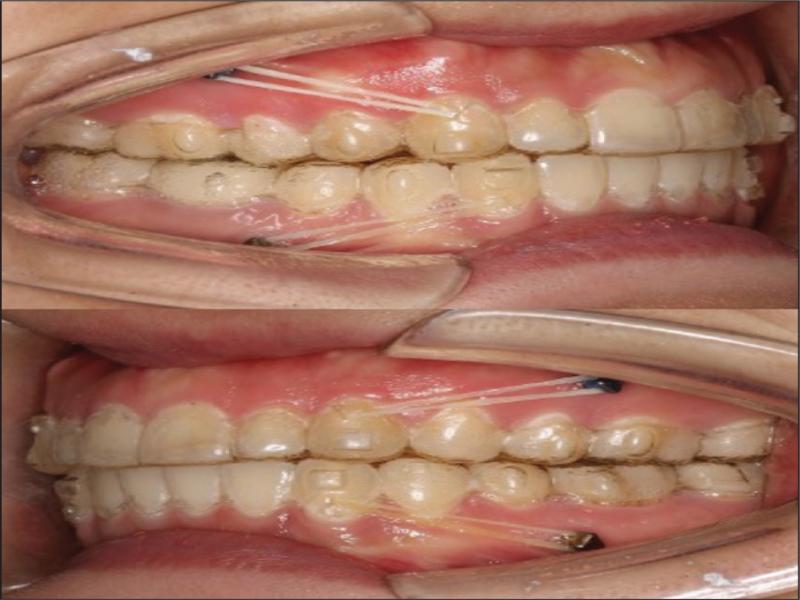

Option two: Invisalign treatment to distalise both dental arches, retract and retrocline the upper and lower incisors, and to decrease the lip prominence. Miniscrews would be required to reinforce posterior anchorage. Elastics applied between the miniscrews and precision cutouts in the clear aligners would be used to achieve the distalisation of both arches (Figure 4). The third molars 28, 38 and 48 would be extracted; the 18 was not extracted but monitored during treatment because it was affected by microdontia and in a high position with an expected inconsequential impact on the distalisation of the dentition in the respective quadrant. The extraction of the deeply impacted 18 was likely to involve risks of tearing of tissue flaps and the excessive removal to bone and overlying soft tissue (Figure 3).

Intraoral photographs showing the elastics running from the precision-cuts to the miniscrews.

In the first trial, a total of 30 aligners (19 upper and 11 lower aligners involving six months of treatment) were used to level and align both dentitions and to distalise both arches. No interproximal reduction was planned during this stage. A miniscrew (length of 10 mm and diameter of 2 mm; Ormco Corporation, CA, USA) was inserted between the second premolar and first molar in each quadrant. Precision cutouts (hooks on canines) were prescribed in the aligners (Figure 4). According to Align Technology’s instructions, the patient was required to wear each aligner with elastics (200g force on each side, size 1/8, 3.5 oz) between the precision cutouts and miniscrews for at least 22 hours per day for 10–14 days in order to distalise both dental arches (Figure 4). However, no clinically significant improvement was observed in the retraction of the lips nor improvement in the molar relationships after the first 100 days of treatment. The upper and lower midlines remained 1 mm and 2 mm to the left of the facial midline, respectively (Figure 5). Therefore, a refinement was required before attempting further distalisation of the dentitions.